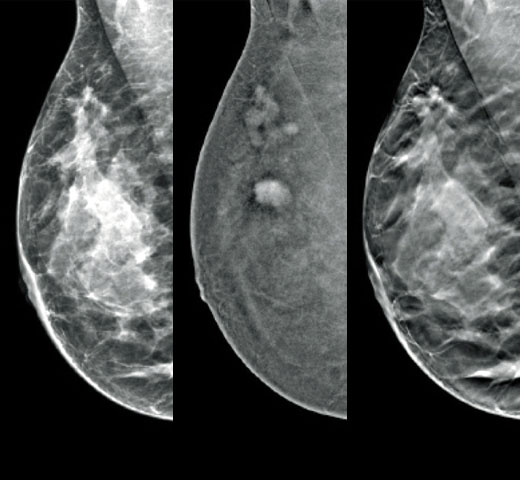

Imagens de mamografias